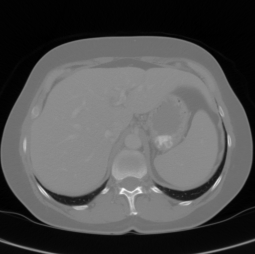

2.2 Data Preparation

The following section deals with data preprocessing and augmentation for CT data. Pre-processing was carried out in a slice-wise fashion. First, the Hounsfield unit values were windowed in the range [100,400]100400[-100,400] to exclude irrelevant organs and objects. Figure 3 shows the effect of our applied preprocessing to a raw medical slice. We increased contrast through histogram equalization. Figure 3 shows also the final slice after HU-windowing and contrast-enhancement. The contrast within the liver has been enhanced to allow better differentiation of abnormal liver tissue. For DW-MRI the data preparation scheme is similar and differs in the data normalization, which additionally performs N4bias correction [28].

Figure 3: Overview of the applied preprocessing steps. The raw CT slices (left) are windowed to a Hounsfield Unit range of -100 to 400 HU to neglect organs and tissues that are not of interest. The HU-windowed slice (middle) is further processed using a histogram equalization to allow further contrast enhancement of abnormal tissue (right).